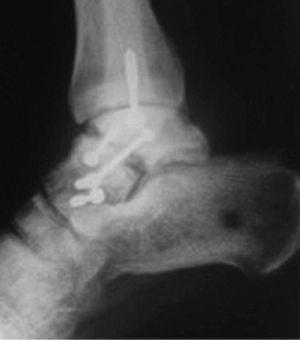

En las fracturas del cuerpo del astrágalo (7 casos) se realizó reducción abierta mediante un abordaje medial con osteotomía del maléolo tibial para visualizar todos los planos de la fractura y fijación interna (RAFI) con tornillos o agujas de Kirschner, o ambos. En 2 casos se realizó un abordaje bilateral debido a la complejidad de la fractura (fig. 6).

Fig. 6. --Fractura abierta de cuello de astrágalo (tipo III de Hawkins) y tratamiento realizado. Radiografías a los 16 meses.

Fig. 6. --Open fracture of the astragalus neck (Hawkins type III) and treatment carried out. Radiographies at 16 months.